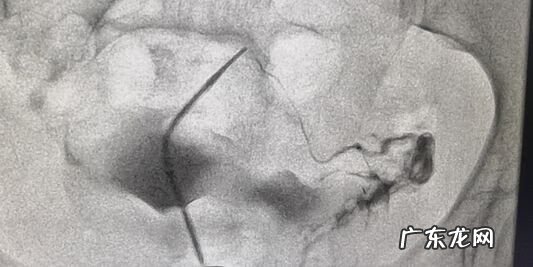

患者 , 28岁 , 结婚1+年 , 性生活正常未孕 , 诊断为:原发性不孕 。造影提示右侧输卵管堵塞 , 介入治疗后已孕28周 。

文章插图